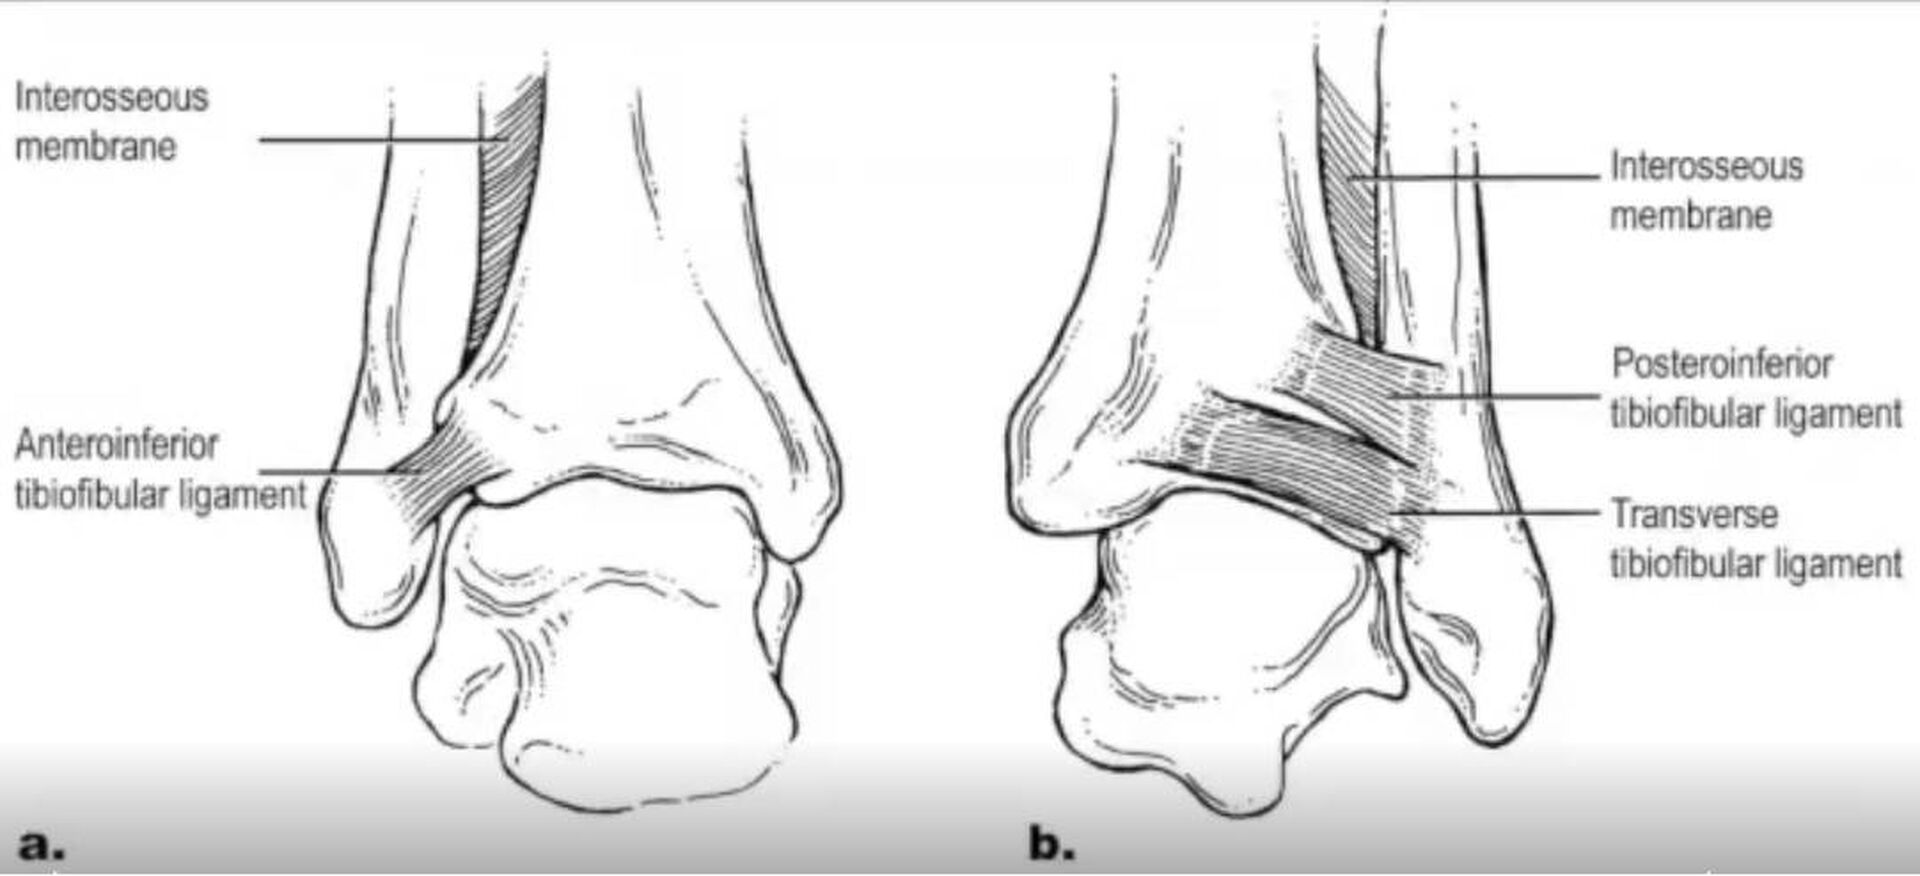

Les traumatismes en rotation sont particulièrement dangereux car la chaussure de ski ne limite pas ce mouvement. Les ligaments entre le tibia et le péroné sont susceptibles d'être rompus, entraînant des douleurs importantes.